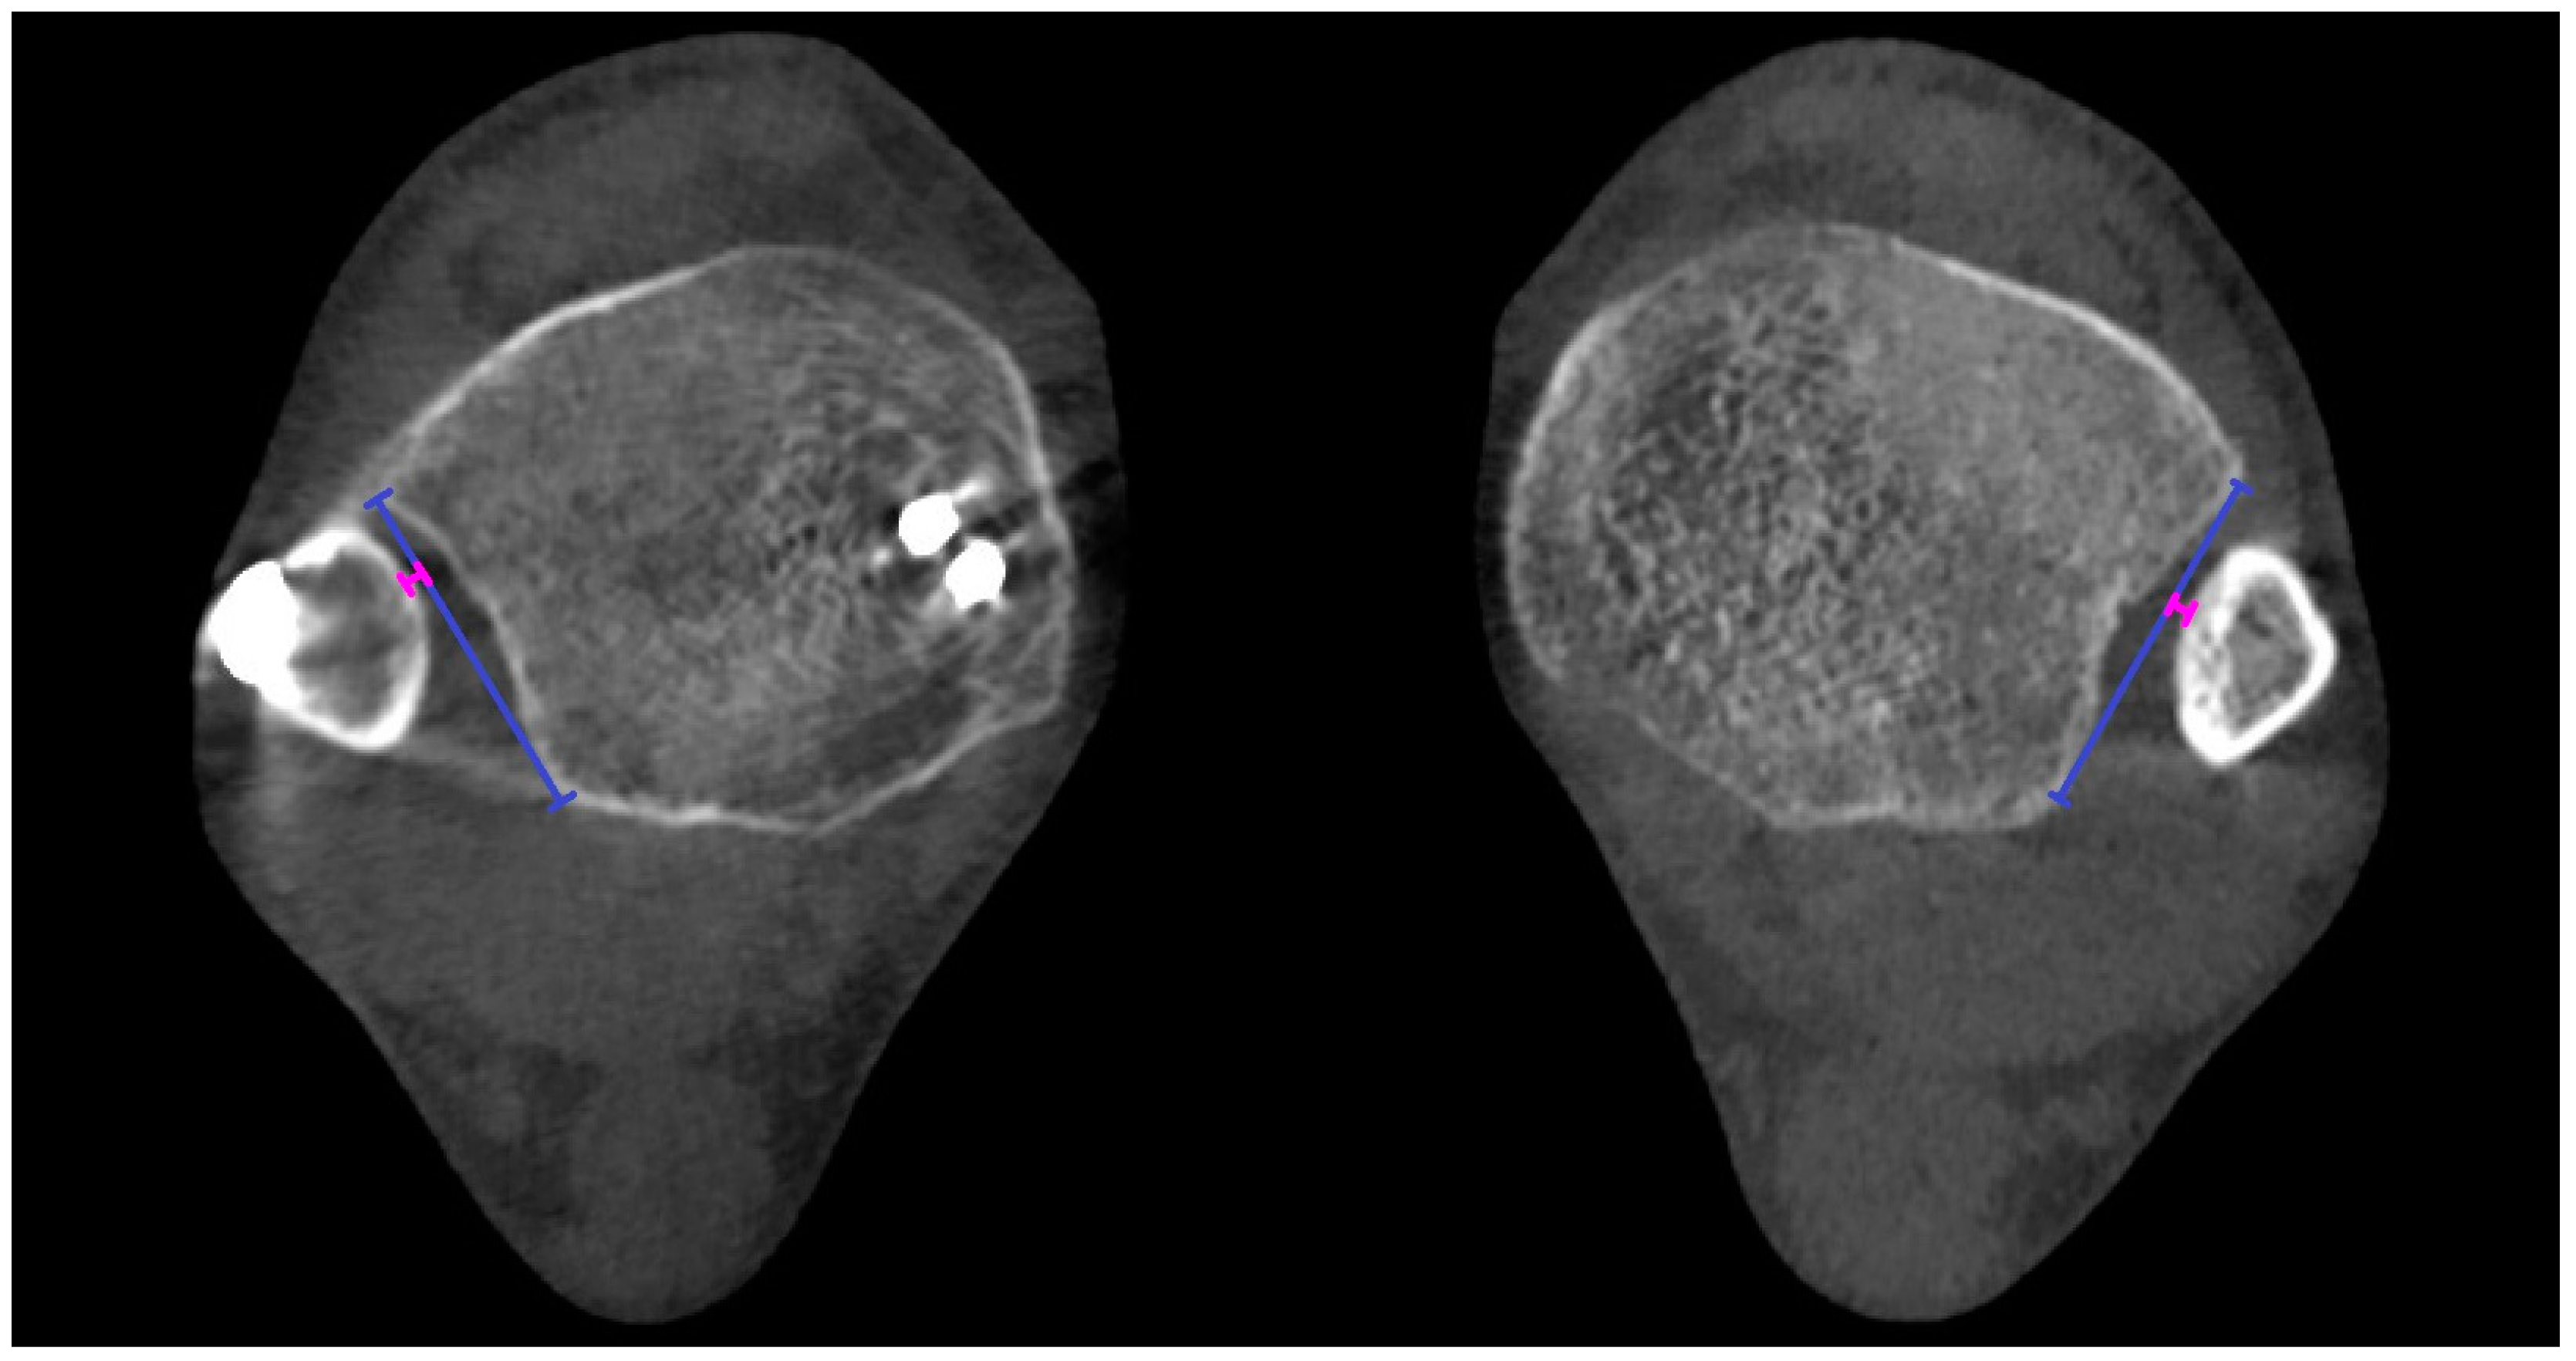

Figure 7. Torsion of the fibula (torsion) angles measured in both ankles. Measurements were taken in the axial plane, 5, 6, and 7 mm distal to the lateral margin of the tibial plafond. Orange lines represent the articular surfaces of the lateral and medial malleolus of the unaffected ankle, while light-blue lines correspond to the affected ankle. The angle of the unaffected ankle is measured between the orange lines, and the angle of the affected side is measured between the light-blue lines. Dark blue represents transverse line which is not relevant for the measurments.